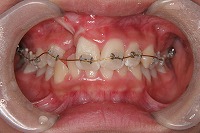

反対咬合を主訴に来院された、右側唇顎裂の10歳6ヵ月の女の子です。診断「右側唇顎口蓋裂で反対咬合を伴う」1期治療で反対咬合の解消と上顎の前歯の並びを修正しました。2期治療は抜歯をせず治療を行いました。